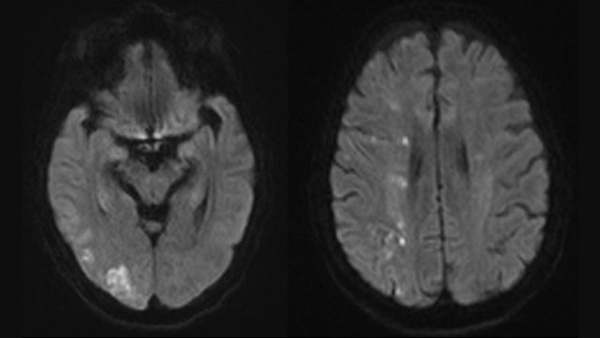

Dive into a curated collection of compelling clinical cases shared by leading experts from LINNC Paris, LINNC Seminars, and LINNC online. Discover a diverse array of complex cases, including aneurysm embolization, AVM/fistula management, stroke interventions, and cSDH treatment. Each case study provides an in-depth exploration of advanced procedures, innovative techniques, and their real-world applications in diagnosing and managing neurovascular conditions.

One&Done technique with optiMAX large volume coil

Stent assisted coilingAneurysms